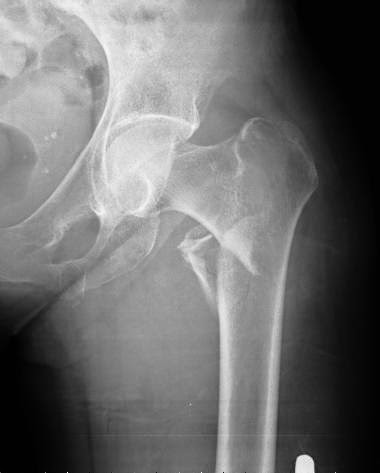

Eficacia de un programa poblacional de rastreo de osteoporosis en mujeres de 70 a 85 años

Se calculó el puntaje FRAX y se realizó densitometría a aquellas con riesgo de fractura elevado, dejando el tratamiento a criterio del médico de cabecera. Se logró una reducción del 28% (IC 11-41%) de las fracturas de cadera. The Lancet, 15 de diciembre de 2017

Osteoporosis: umbrales de intervención adaptados a cada país

Una revisión sistemática de los umbrales de intervención basados en la herramienta FRAX para la estimación del riesgo de fractura. Archives of Osteoporosis, 27 de julio de 2016